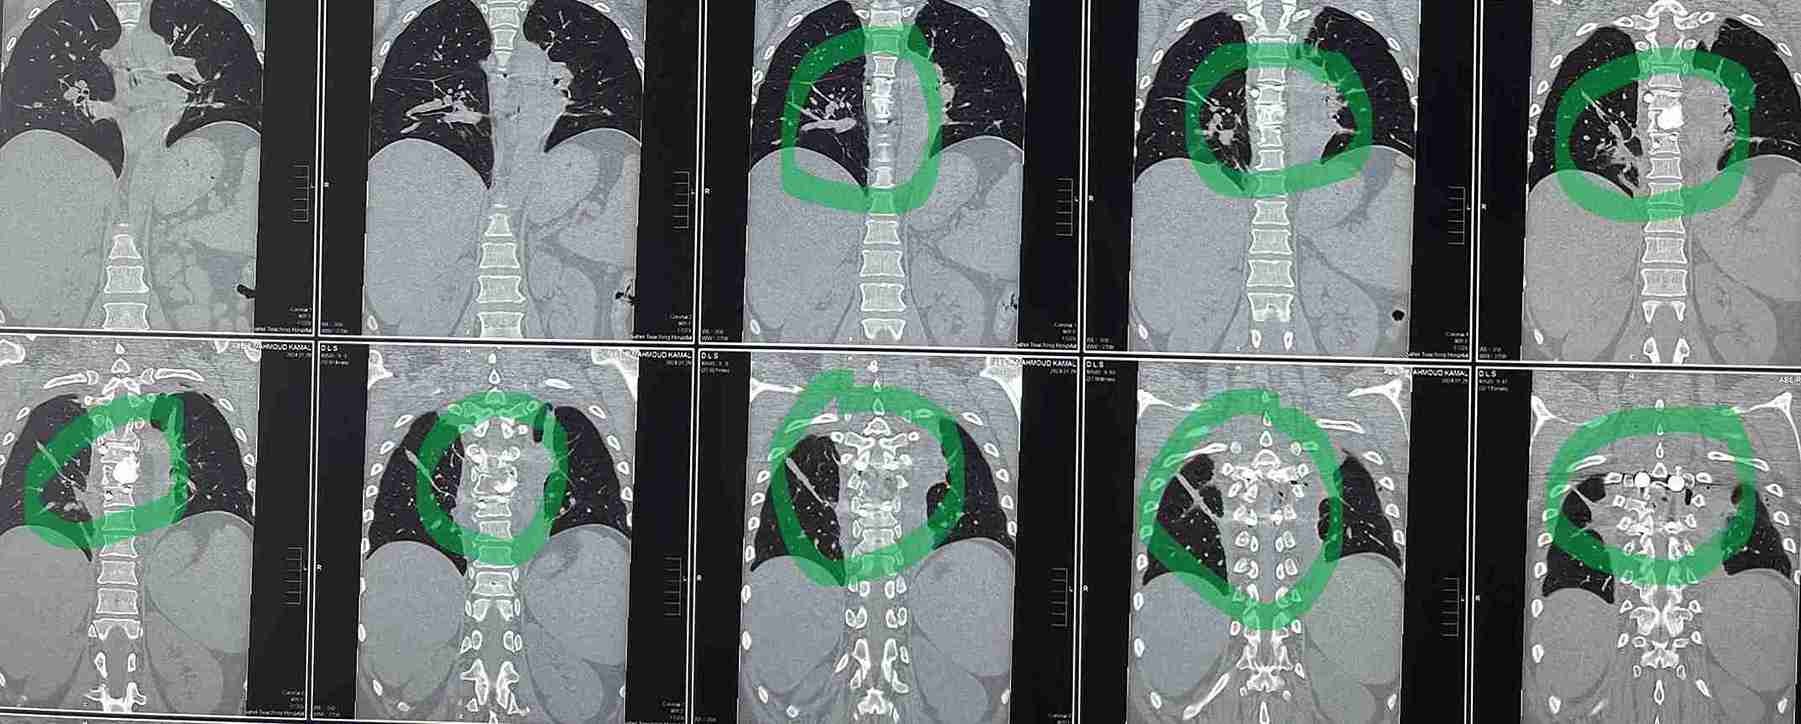

بعد عمل الاشعات تبين وجود ورم التكيس الدموي المتمدد بالفقرة الصدرية السادسة.

تم عمل جراحة ناجحة لاستئصال الورم بجسم الفقرة والتعويض بنظام تثبيت امامي عبارة عن اسمنت عظمي وخلفي عبارة عن مسامير وقضبان  تيتانيوم .

وذلك موضح بصور الاشعات قبل وبعد الجراحة . وقد تحسنت المريضة واستعادت كامل الوظايف العصبيىة واصبحت تمارس حياتها بصورة طبيعية.